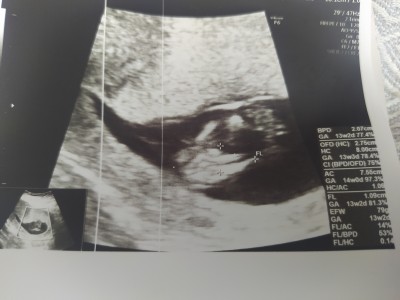

Gebelik haftası

13+0

Kız gibi sanki canım saglicakla al kucağına yanlız burada bu sorular sorulmuyor sohbet bölümünde soruluyor bu bölümde yasak kapatırlar sorunu canım